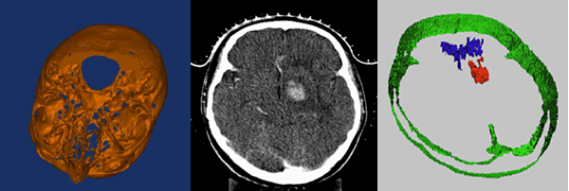

4、三维图像重建及分析

三维重建是指对三维物体建立适合计算机表示和处理的数学模型,是在计算机环境下对其进行处理、操作和分析其性质的基础,也是在计算机中建立表达客观世界的虚拟现实的关键技术。

8、石油地质图像处理应用系统开发